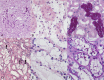

Activation of the PI3K/AKT/mTOR pathway is a crucial molecular event in human clear cell renal cell carcinoma (ccRCC), and is also upregulated in diabetic nephropathy. In diabetic rats metabolic changes affect the renal distal tubular epithelium and lead to glycogen-storing Armanni-Ebstein lesions (AEL), precursor lesions of RCC in the diabetes induced nephrocarcinogenesis model. These lesions resemble human sporadic clear cell tubules (CCT) and tumor cells of human ccRCC.Human sporadic CCT were examined in a collection of 324 nephrectomy specimen, in terms of morphologic, metabolic and molecular alterations, and compared to preneoplastic CCT and RCC developed in the rat following streptozotocin-induced diabetes or N-Nitrosomorpholine administration. Diabetic and non-diabetic rats were subjected to the dual PI3K/mTOR inhibitor, NVP/BEZ235.Human sporadic CCT could be detected in 17.3% of kidney specimens. Human and rat renal CCT display a strong induction of the PI3K/AKT/mTOR pathway and related metabolic alterations. Proteins involved in glycolysis and de novo lipogenesis were upregulated. In in vivo experiments, dual inhibition of PI3K and mTOR resulted in a reduction of proliferation of rat diabetes related CCT and increased autophagic activity.The present data indicate that human sporadic CCT exhibit a pattern of morphologic and metabolic alterations similar to preneoplastic lesions in the rat model. Activation of the PI3K/AKT/mTOR pathway in glycogenotic tubuli is a remarkable molecular event and suggests a preneoplastic character of these lesions also in humans.